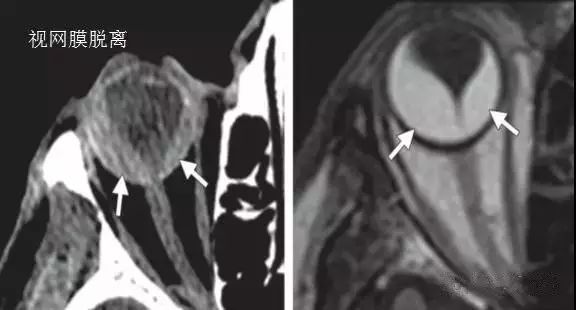

后段损伤

由于视网膜牢固地固定于后方的视神经盘上 , 因而脱离的视网膜在影像学上可形成特征性的尖端位于视神经盘的V型表现 。

当眼压降低的时候 , 脉络膜上腔的压力也会降低 , 使得液体或血液积聚 , 从而导致脉络膜分离 。 通常 , 脱离的脉络膜在影像学上表现为凸透镜样或双凸状 , 眼球后部不受累 。